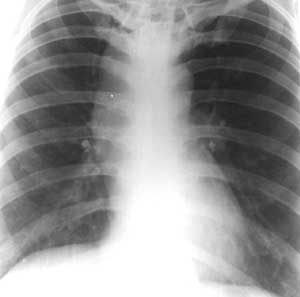

Рис. 1. Ахалазия. Дилатированный пищевод расширяет средостение вправо.